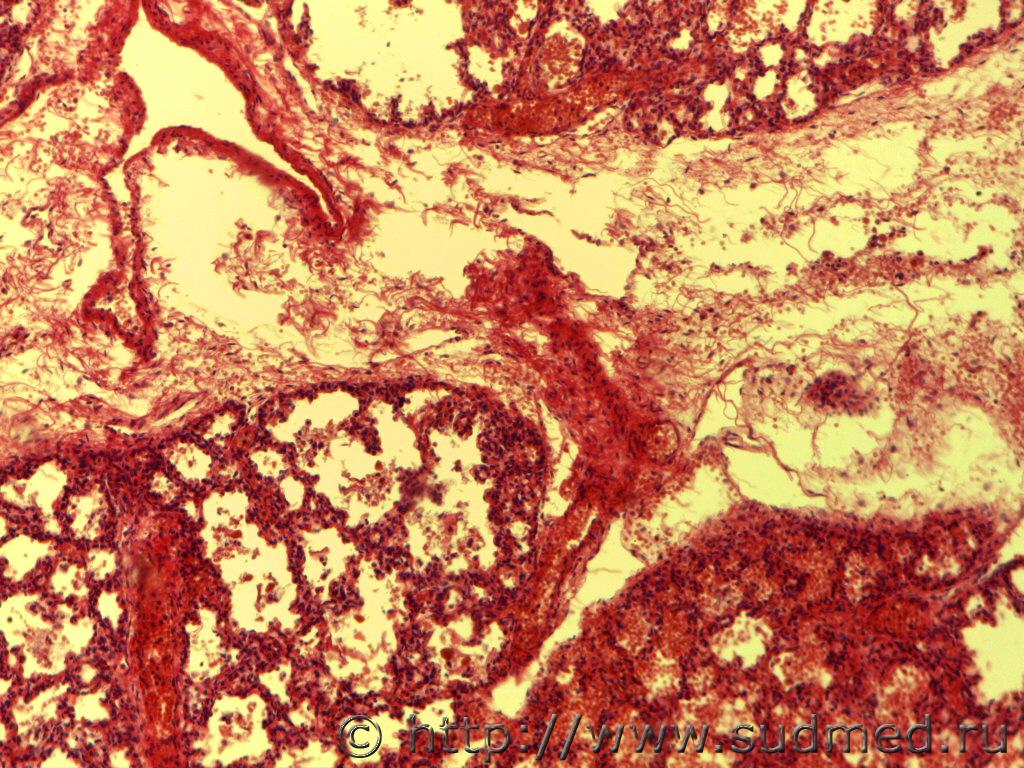

Здравствуйте, уважаемые эксперты! я начинающий гистолог, помогите разобраться с легкими - дышавшие или нет? Девушка 1986г.р. рожает первого ребенка, ребенок родился мертворожденным, беременность проходила хорошо, роды в срок, жалоба на врача, что во время схваток к ней долгое время никто не подходил. Танатолог берет 4 кусочка легких, в\д,ср\д левого легкого, ср\д, н\д правого легкого, легочные пробы - легкие в воде тонут. Со слов врачей ребенка пытались реанимировать, никаких записей это подтверждающих нет. То что там аспирация околоплодными водами очевидно, меня смущает полное расправление всех альвеол, даже эмфизема.

фото прилагаю

(6-е и 8-е фото окраска по Ван Гизону)

1.Расправленные в результате самостоятельного дыхания терминальные дыхательные пути имеют чёткие очертания без признаков острой эмфиземы - такой картинки не вижу.

2.При искусственном дыхании расправляются некоторые альвеолы,но полного расправления лёгких не наблюдается.Характерным считается проникновение воздуха в верхние доли,в том числе и верхушки лёгких,по передненижним краевым зонам и по междолевым поверхностям.Главным признаком искусственной вентиляции лёгких является острая эмфизема с нарушением целости респираторной паренхимы.Эмфизематозные изменения имеют характер структурных нарушений в виде разрывов межальвеолярных перегородок с образованием эмфизематозных очагов,окружённых участками дистелектаза.

3.Мне представляется,что на фото лёгкие после искусственной вентиляции.

Добрый день! наблюдается неполное расправление просвета альвеол, альвеолярные перегородки извилистые, широкие междольковые прослойки, просвет альвеол местами выполнен свежей кровью, с примесями десквамированных альвеолоцитов, встречаются овальные, кубические альвеолоциты, местами и в просвете отдельных бронхиол имеется примеси свежих эритроцитов. В просвете альвеол единичные фрагменты роговых чешуек( в присланных Вами микрофото), которые не может быть признаком массивной аспирации, т.к. внутриутробно в норме до бифрукации в просвете трахее бывает околоплодные воды. Участков ателектаза и острых очагов эмфиземы не видно в микрофото.

Мое предварительное мнение по присланным микрофото Респираторный дистресс-синдром новорожденных. Тонут легкие и при кровоизлиянии в респираторные отделы легких.